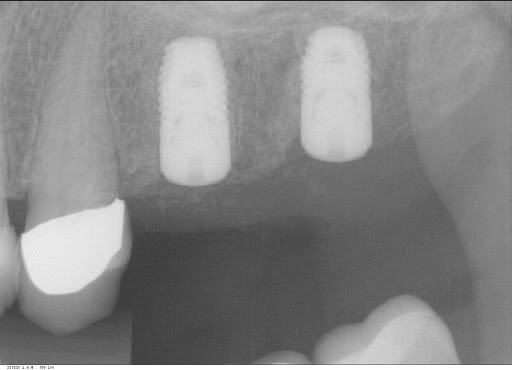

Photos